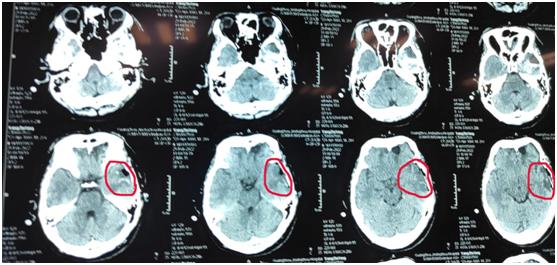

看着面容削瘦说话有气无力的史道贫,唐运林教授明白他的病情并不容乐观!毕竟距离他少年时发生的车祸已经14年过去了,是否是车祸引起的癲痫还是个未知数,时值周末假期,唐运林教授得知史道贫情况后,为了进一步检查,迅速安排人员加班,在当天为他完成了影像检查发现。

要明确癫痫诊断,就必须找准癫痫病灶位置。这一过程正以唐运林教授为首的神经外科、影像学等专家团队共同完成的,是经过跨学科、跨专业的缜密讨论后,具体选用定位检查的手段组合,不论是无创伤性检查,还是有创伤性检查,至少应该包括发作期和发作间歇期的脑电图及发作症状的定位分析、头磁共振(MRI)、神经心理学检查等。经查确诊史道贫正是脑部受损引发癲痫,原来正是14年那场车祸遗留了病根!当时年少的他由于没有外伤所以只去了小镇医院做体检,真相大白后,唐运林教授对病情进行详细评估,为他制定了手术治疗方案。